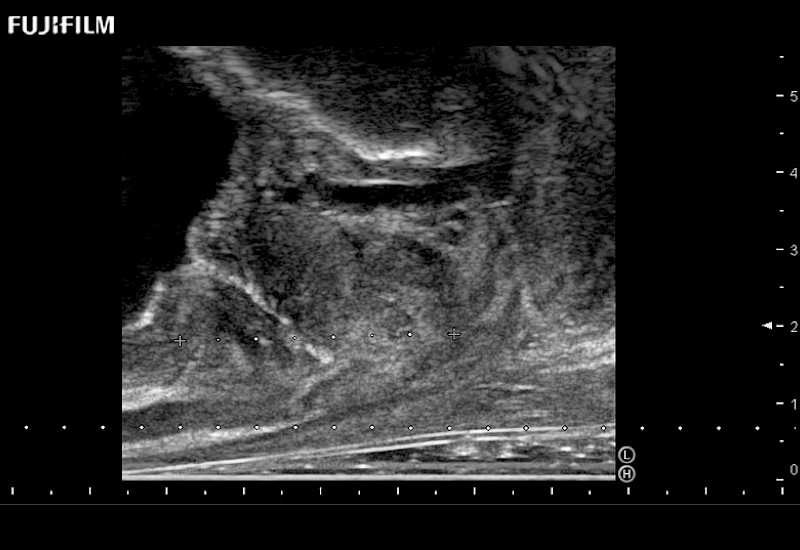

Ideal transducer for Transperineal Biopsy, Hydrogel Spacer Placement, Brachy LDR & HDR, Cryo, and MPMRI procedures.

Main Specifications: